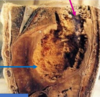

9

Opened stomach

Ulcer with raised everted edges and rough necrotic floor

enlarged pre-pyloric lymph nodes

Ulcerative carcinoma (malignant) of the stomach

Gastric lymph node metastases